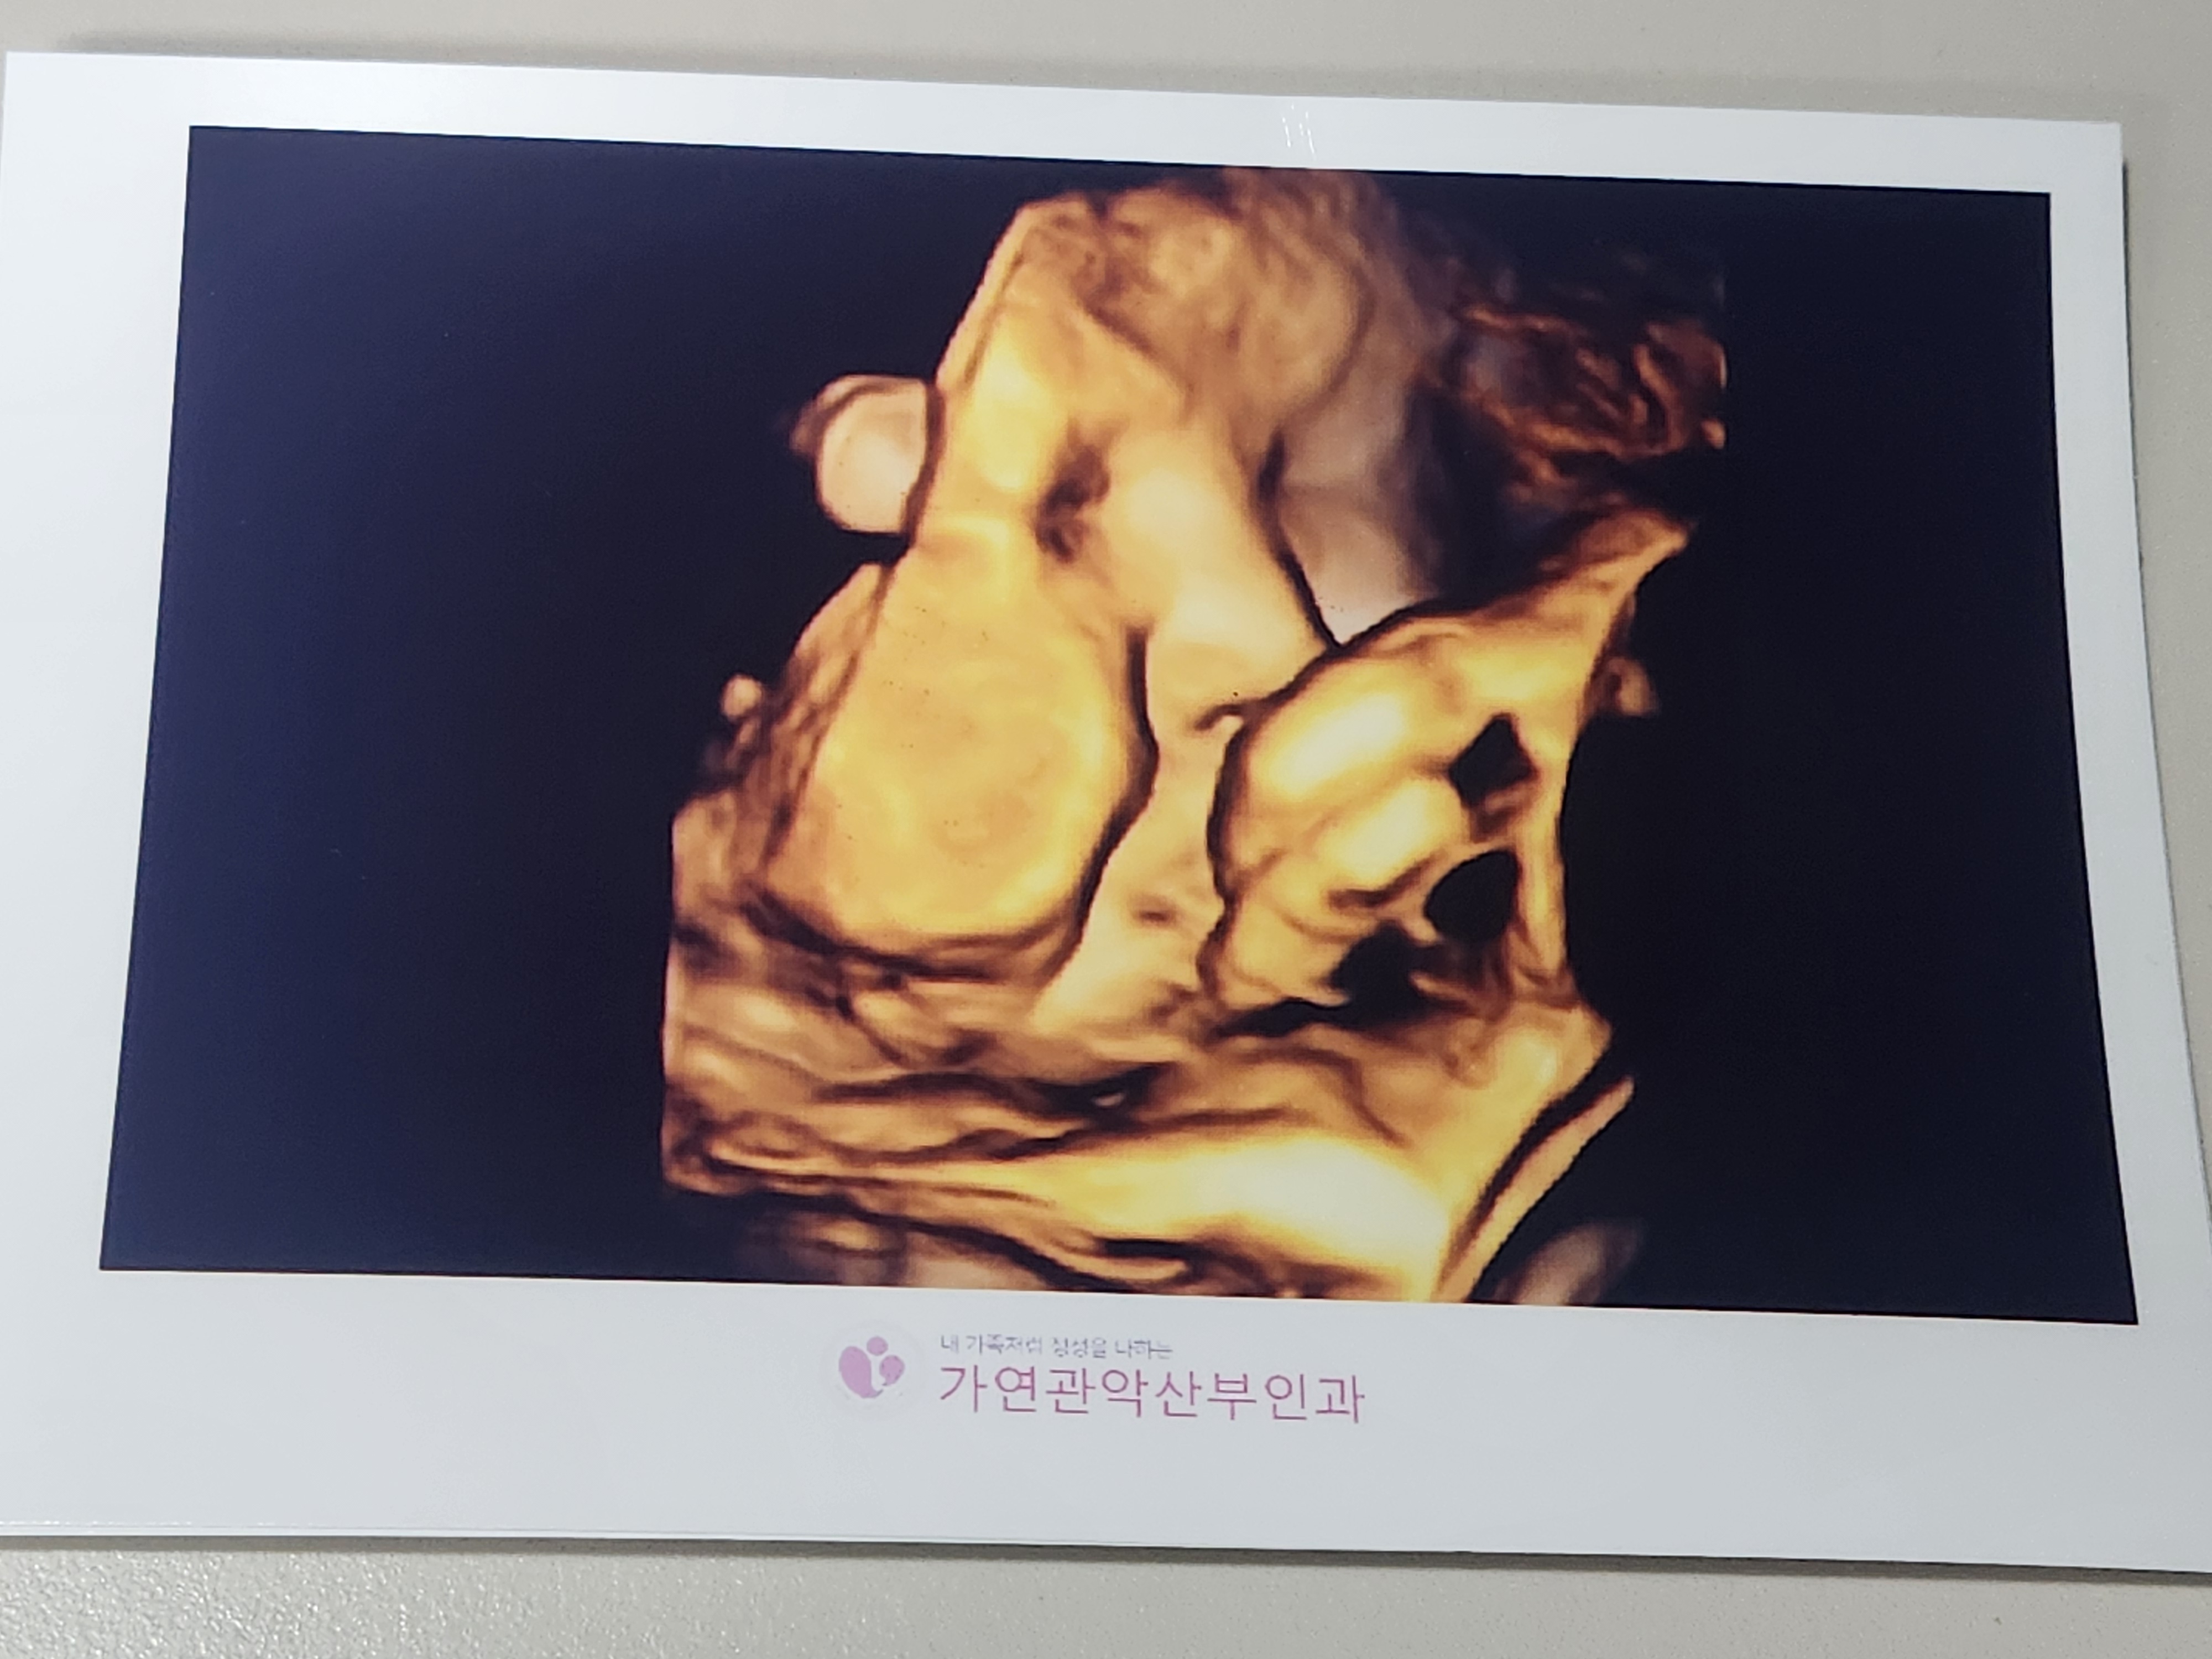

태동검사가 끝난 후 초음파 검사를 했습니다.

또 얼굴을 가린 복덩이지만, 그 사이에 볼살이 귀여워진 복덩이입니다.

초음파 검사상 자연분만 하기에 상태도 아주 좋다고 하셨습니다.

태아는 37주에 2.5kg이었으며, 원장님께서 37주 이상 2.5kg이상이면 지금부터 언제나와도 정상분만이라고 하셨고, 언제나와도 이상하지 않은 주수라고 마음에 준비를 하시라고 말씀해주셨습니다.